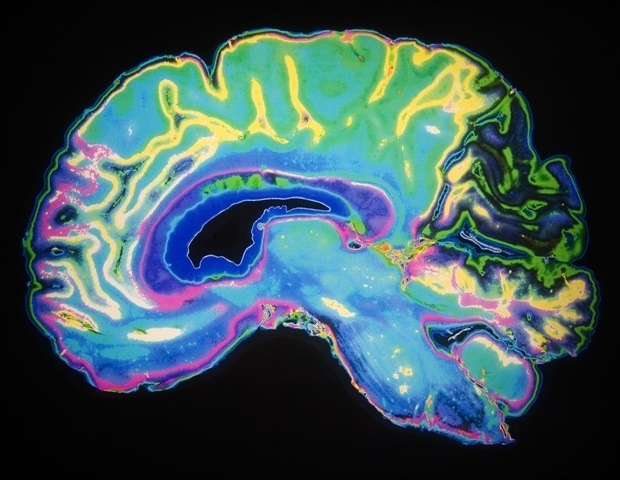

Recent research from the Technical University of Munich (TUM) and the Friedrich-Alexander-University Erlangen-Nuremberg (FAU) has revealed that functional MRI (fMRI) signals can often misrepresent true brain activity. The study indicates that in approximately 40 percent of cases, an increased fMRI signal correlates with reduced brain activity, challenging a fundamental assumption in neuroscience.

The study involved over 40 healthy participants who were given tasks that typically produce predictable fMRI signal changes, such as mental arithmetic and autobiographical memory recall. During these tasks, the researchers employed a novel quantitative MRI technique to simultaneously measure actual oxygen consumption.

The results varied depending on the task and the specific brain region. For instance, areas engaged in calculation showed increased oxygen consumption without corresponding increases in blood flow. Instead, these regions were found to extract more oxygen from a stable blood supply, using the available oxygen more efficiently without necessitating greater perfusion. This discovery has significant implications for understanding brain function and energy metabolism.